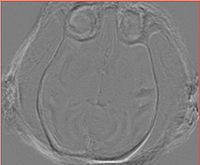

Same slice, difference between 2 and 3

• Nov 13, 2009: A significant non-rigid discrepancy between the registered image produced by BRAINSFit and the image resampled with the ResampleVolume2 and the transform produced by BRAINSFit.